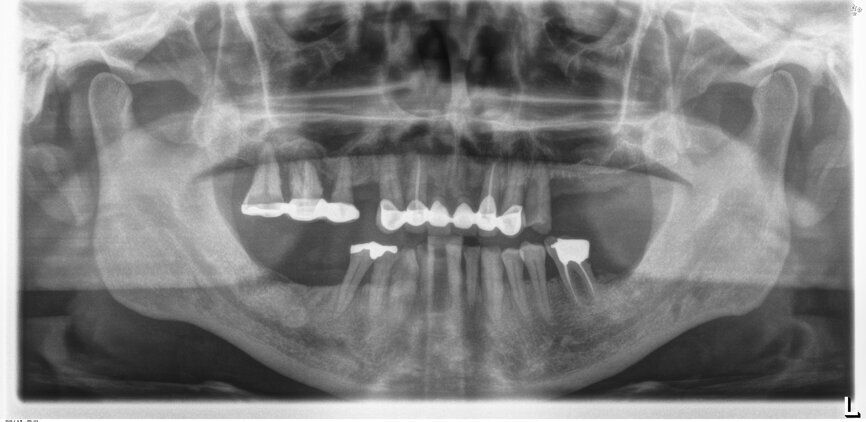

A 51-year-old male patient who was a smoker (< 10 cigarettes per day) and in good general health presented to the clinic with missing molars in the second and fourth quadrants, Grade III mobility of teeth #24 and 17, decayed roots and gingival inflammation, and without abscess or sinusitis of tooth #16. The anterior zone showed  different extents of recession, bone resorption and deep periodontal pockets around teeth #12 and 22, which led to the patient complaining about an aesthetically unsatisfying restoration (Figs. 1 & 2).

On the day of surgery, we prepared for the surgical protocol provided by the implant planning software, which guided us on the drilling sequence and the use of the appropriate instruments for the implant bed preparation (Figs. 30a & b). After the fixation pins had been allocated, teeth #17, 16, 15, 13, 12, 22, 23 and 24 were atraumatically extracted and alveolectomy was performed using a bone reduction guide (Figs. 31–36). Four implants (Straumann BLX; regular base; diameter: 4.5 mm; length: 12.0 mm) were placed, two straight implants in the anterior and two titled implants in the posterior. All the implants were stabilised to a torque of 50 Ncm (Figs. 37–43), and the SRAs were placed on top. The SRAs on the posterior implants had an angulation of 30° (diameter: 4.6 mm; gingival height: 3.5 mm) and on the anterior implants an angulation of 17° (diameter: 4.6 mm; gingival height: 3.5 mm; Figs. 44 & 45).

Five-day follow-up